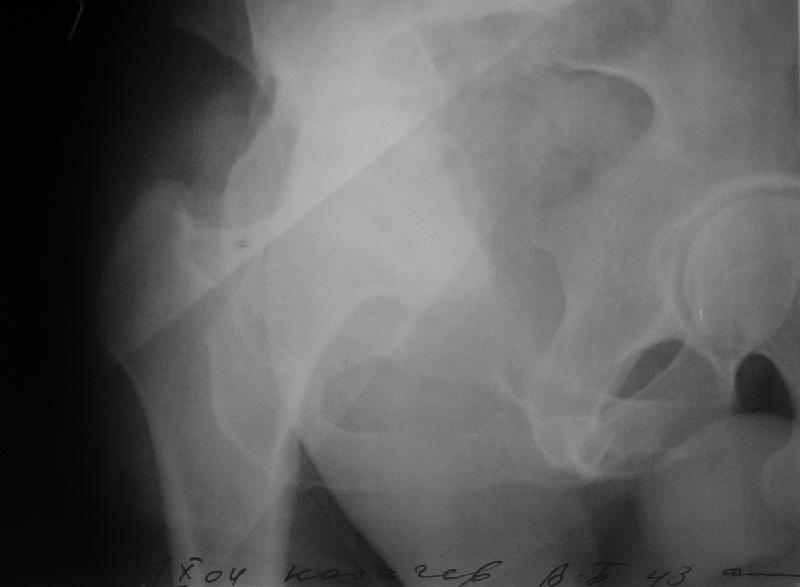

мужчина, 43 лет, получил травму в январе 2001 года. Лечился консервативно, в соседней области: скелетное вытяжение 6 недель, далее в кокситной гипсовой повязке 2 месяца. С декабря 2001 года ходит без дополнительной опоры, с компенсацией имеющегося укорочения - 4 сантиметра. С марта этого года беспокоят боли, усиливающиеся после умеренной физической нагрузки, возникающие в задних отделах таза и переходящие в область тазобедренного сустава. По данным ретгенографии и компьютерной томографии у больного имеется несросшийся высокий двухколонный перелом вертлужной впадины. Заранее спасибо.